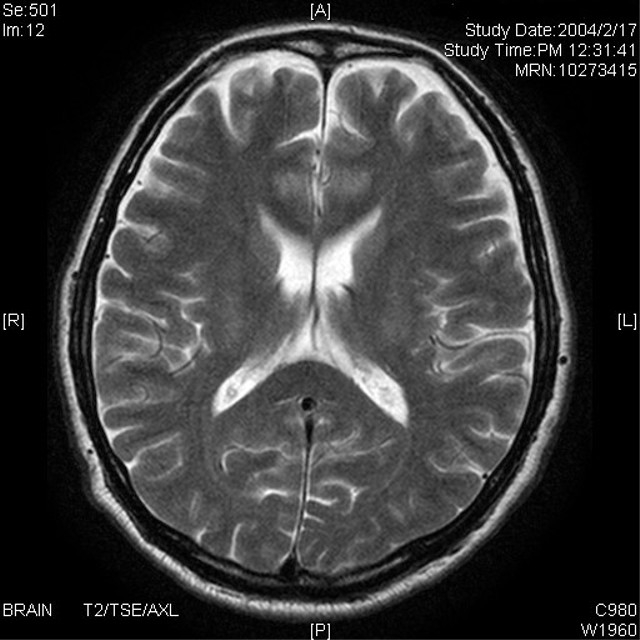

私のフォロワー全員に知って欲しいんだけど最近私の病院20~30代で脳梗塞起こして入院してる人すごく多いんだよね。脳梗塞って時間との勝負だから異常を感じら即119してほしい「一晩様子を見たけど改善しないから翌朝受診したら脳梗塞だった」ってパターンが多すぎるんだよ…画像は参考用の判断基準 pic.twitter.com/HCmBABN9n3

更に知ってほしいことをお伝えしますが画像のような症状がでても数分~1時間程で症状がおさまる場合でも必ず受診してください。それは一過性脳虚血発作といって1度脳血管が詰まって神経症状がでてもなんらかの事情で詰まりが解消されて症状が消える状態です。脳梗塞を起こしやすい状態なんです

FF外から失礼します。脳梗塞の症状としては画像のようなものがあげられますが、突如として視野の欠如も起きます。去年祖父がその症状で病院に行ったところ、脳梗塞と診断されました。どこで血管が詰まっているかによって症状が異なるようです。私の祖父は視力に影響が出た部位でした。